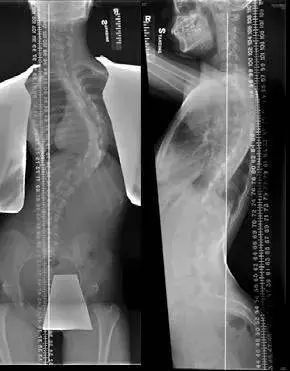

原发性脊柱侧弯约占所有个案的八成至八成半。患者的脊椎在出生时并无异样,其后脊椎在童年时逐渐变型。部分病人于幼儿及小童期已经出现脊柱侧弯症状,但普遍个案发病的年纪是在 10 至 15 岁之间(图 1 , 2)。2-3% 的青少年出现不同程度的脊柱侧弯。患有轻度脊柱侧弯的男女比例是差不多,然而女生患有严重脊柱侧弯的比率是男生的 8 倍。近期有研究显示,每三个儿童的父母患有脊柱侧弯,就有一个儿童有同样的问题,因而此病被认为部分是属于遗传性的 [2, 3]。可惜,现时仍未能确认引致脊柱侧弯的基因。大众对脊柱侧弯的一般理解是:它会引致明显的背痛或功能受损。

图 2 同一病人正前方及侧面的X光造影。